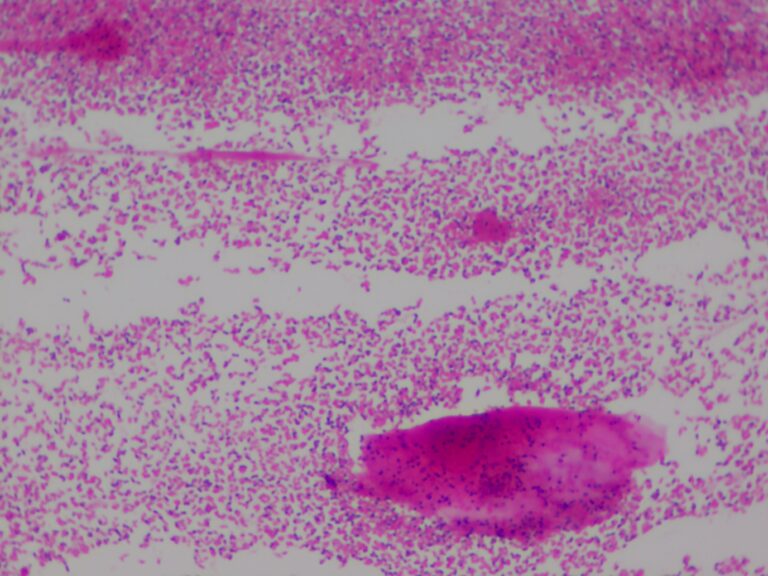

4. MICROSCOPIA DE CONTEÚDO VAGINAL – O QUE É E PARA QUE SERVE

A microscopia do conteúdo vaginal é um exame simples feito no consultório, onde uma amostra do corrimento vaginal é analisada no microscópio. Esse exame permite observar diretamente a presença de fungos, protozoários, além de avaliar o pH vaginal, a quantidade de leucócitos (células de defesa) e a integridade da flora vaginal.

Esse método é especialmente útil em mulheres que apresentam corrimentos de repetição, que já usaram vários tratamentos sem melhora ou que recebem diagnósticos diferentes a cada consulta. Ao analisar o material diretamente, o exame ajuda a identificar com mais precisão a causa do desconforto e escolher o tratamento mais adequado para cada caso.

É um exame rápido, indolor e com resultados imediatos, que pode fazer toda a diferença na conduta clínica e no bem-estar da paciente.